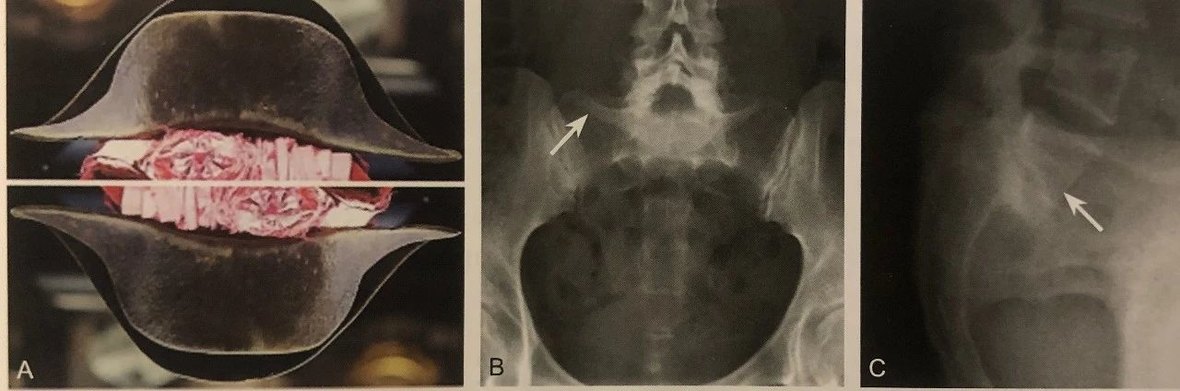

海 鸥 征

A.患者外伤后出现髋臼塌陷,髋臼压缩骨折形成飞行海鸥样改变,即海鸥征(箭头);B.患者髋臼多发骨折合并海鸥征(箭头)

判读要点:

1、髋臼塌陷骨折的表现;

2、髋臼 x 线正位摄片或者 CT 重建可见;

3、最常出现在髋臼前柱骨折或前柱+后半横行骨折;

4、是影响骨折复位质量的独立危险因素。